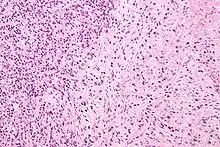

Gleason Pattern 3. H&E stain.

• Pattern 3 - The tissue still has recognizable glands, but the cells are darker. At high magnification, some of these cells have left the glands and are beginning to invade the surrounding tissue or having an infiltrative pattern. This corresponds to a moderately differentiated carcinoma.

Gleason 3 is a clearly infiltrative neoplasm, with extension into adjacent healthy prostate tissue. The glands alternate in size and shape, and are often long/angular. They are usually small/micro-glandular in comparison to Gleason 1 or 2 grades. However, some may be medium to large in size. The small glands of Gleason 3, in comparison to the small and poorly defined glands of pattern 4, are distinct glandular units. Mentally you could draw a circle around each of the glandular units in Gleason 3.[3][6]